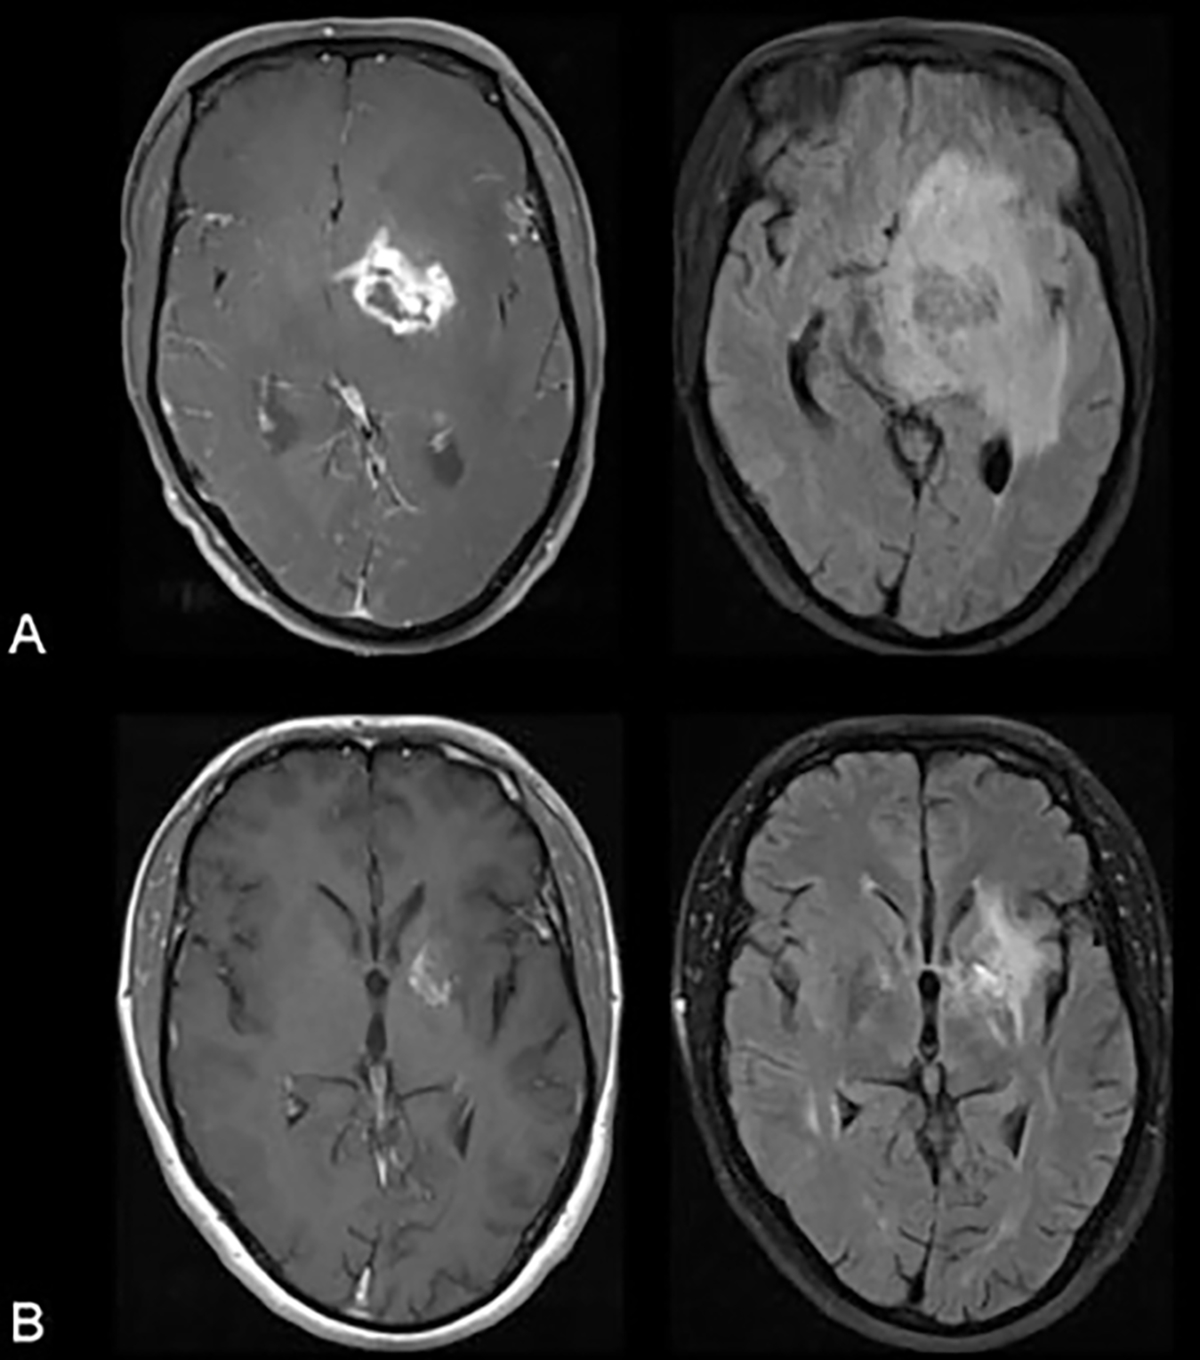

Clinical manifestations of patients with CNS toxoplasmosis include headache, fever, hemiparesis, ataxia, change in level of consciousness and psychomotor retardation; ~ 30% of patients have seizures.127 Almost all of HIV-infected patients with Toxoplasma encephalitis will have detectable serum anti-Toxoplasma IgG, but IgM is rarely detectable because the disease represents reactivation of a chronic infection.128 Often, CSF examination is not helpful in establishing the diagnosis. On CT, there are round, isodense or hyperdense lesion(s) in the hemispheric gray–white junction, deep white matter, or basal ganglia. More than 90% of these lesions enhance with contrast in a ring, nodular, or homogenous pattern. MRI is more sensitive than CT and often identifies multiple lesions (Fig. 2).

Fig. 2.

Biopsy proven cerebral toxoplasmosis in an human immunodeficiency virus-infected patient. (A) Contrast enhanced T1-weighted image (left) and fluid attenuation inversion recovery image (right) at presentation. (B) Corresponding images 5 months after beginning treatment for toxoplasmosis. Courtesy of Christina M. Marra, MD.